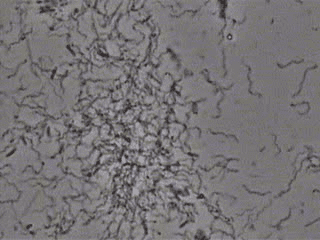

最初の菌の状態です。

カビ、歯周病菌が多数みられます。

1週間後の非常にきれいになった菌の状態です。

本来いるべき正常な菌は残っています。